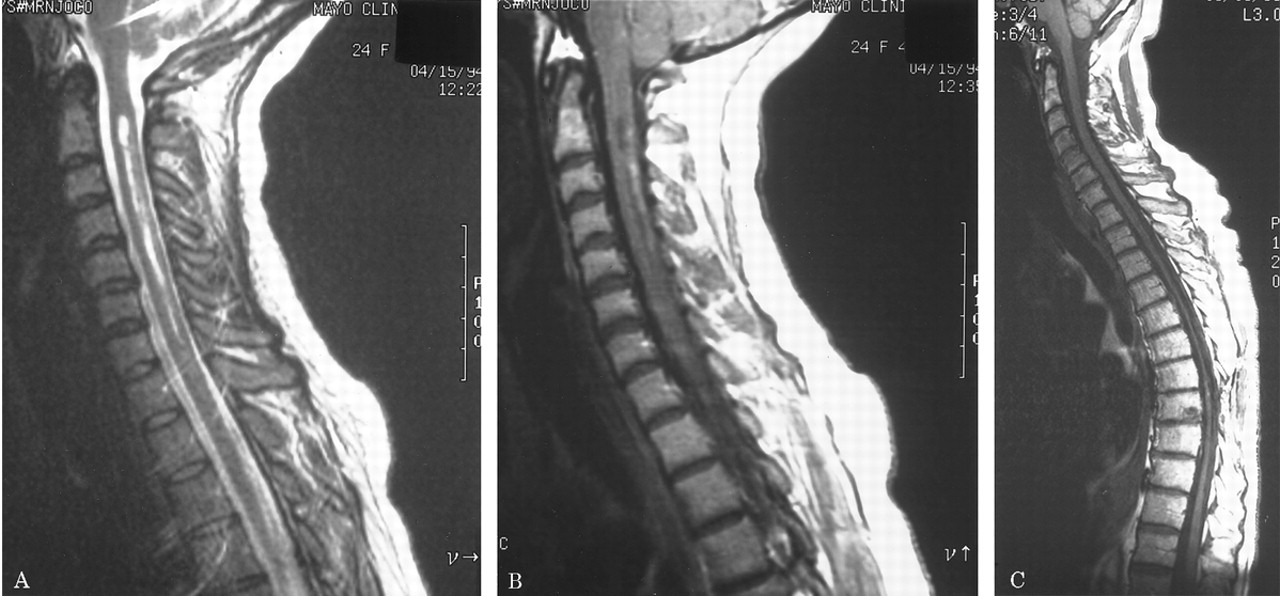

MRI:脊髓。

23复发患者共50脊髓磁共振表现在8周内发病的骨髓炎的情景;47 50(94%)不正常。44 50(88%)、纵向、融合性的损伤扩展在3或更多(通常是6到10)椎段(图5)。索肿胀(25/50扫描,50%)和钆增强(32/50扫描,64%)通常观察到。五23例(22%)与后续线成像发达焦线萎缩。